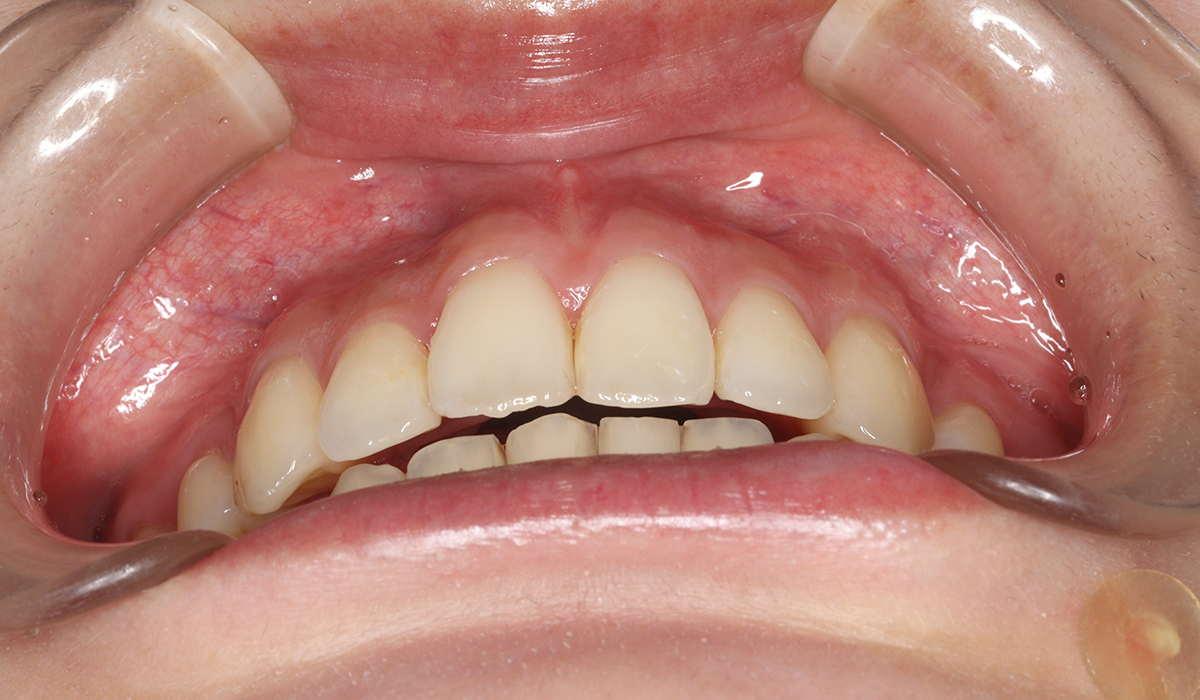

今回ご紹介する患者様は、全体的な歯のガタツキを気にされており、矯正検査後叢生Ⅰ級と診断いたしました。

正面

術前

| 主訴 | 全体的な歯のガタツキが気になる |

| 治療内容 | 全体的な歯のガタツキを気にされており、矯正検査後叢生Ⅰ級と診断いたしました。 |